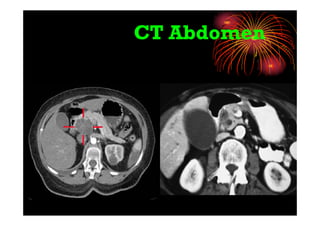

• MDCT : Triple phase CT abdomen: with arterial &

portal venous phase is sensitive to pickup

even small hypodense lesions

CT Abdomen